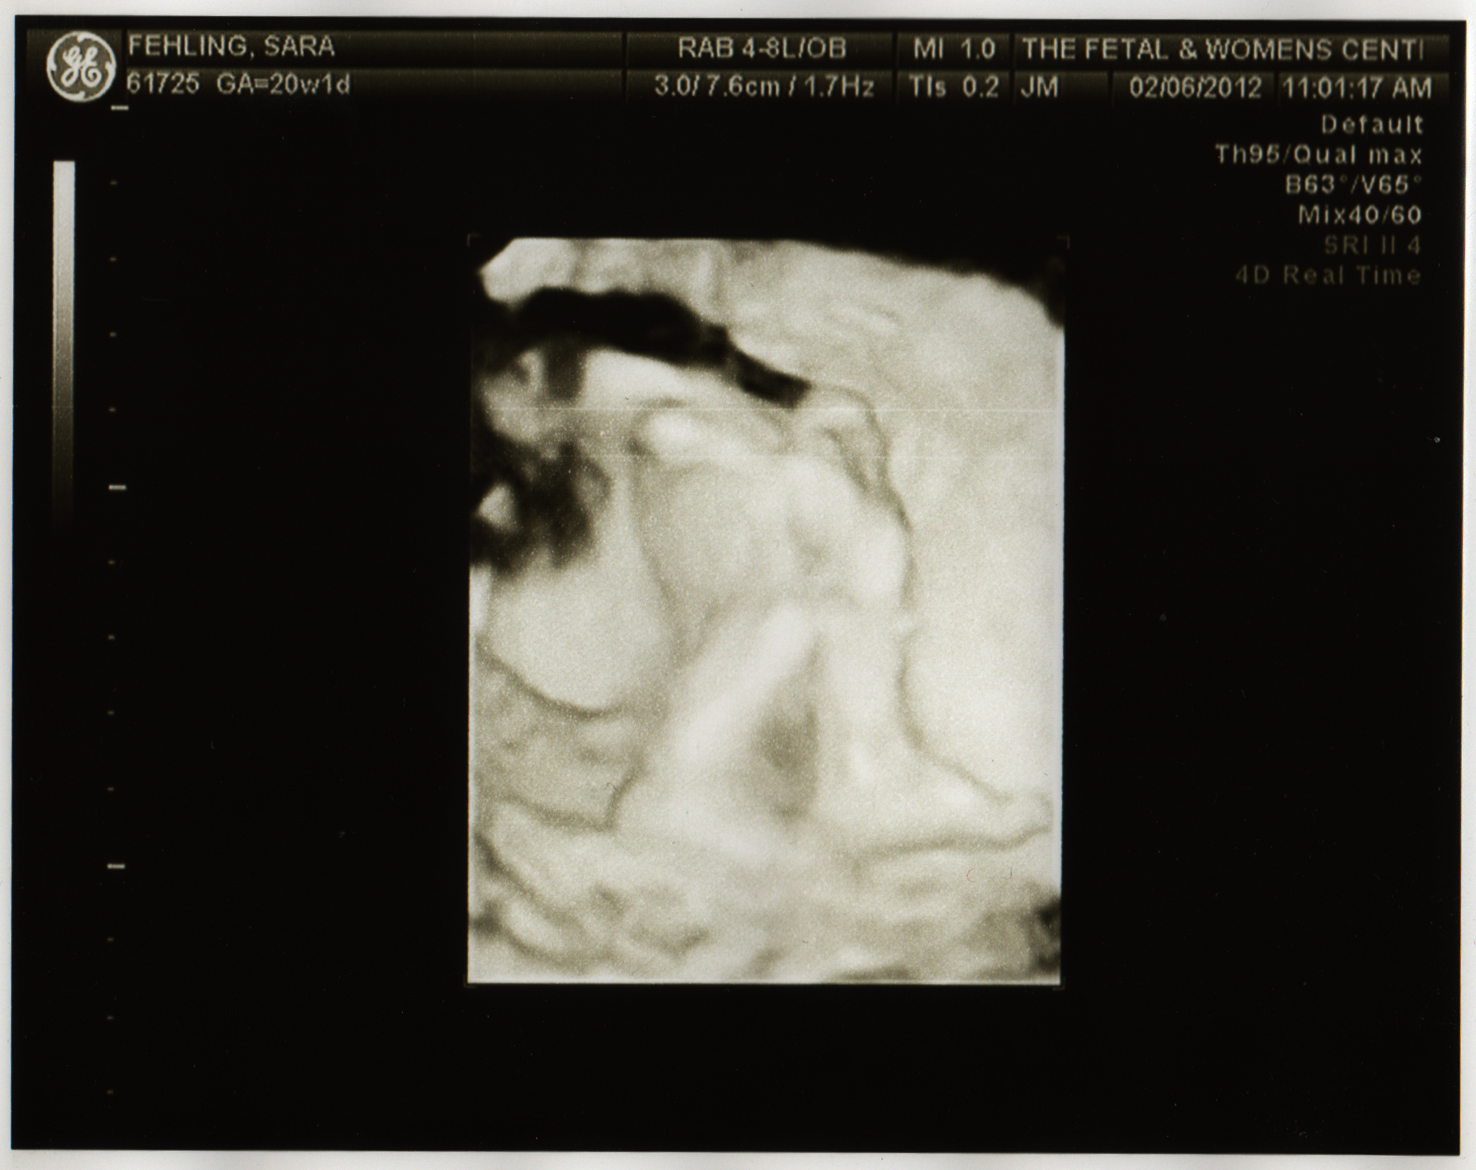

I do have to say though - the other location spoiled me. I've gotten CDs of images from my ultrasound but this time I only got the print outs so I had to scan them. They did do a few 4D images though.

I usually find those extremely creepy, but there's something about getting to (sorta) see your child's face for the first time, months before you know she will be out of your body, is kind of awe-inspiring. Technology is amazing.